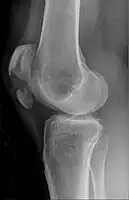

Vertical patella fracture

The patella can break in various ways depending on the way it is injured, and into two or more pieces.[1] Types include transverse, with one fracture line and is the most common type,[5] marginal, osteochondral and the rare vertical type, or stellate, where a direct compression force gives rise to a comminuted pattern.[5][7] Patella fractures can be further classified as displaced, where the broken ends of bone do not line up correctly and separate by more than 2mm, or undisplaced and stable where pieces of bone remain in contact with each other.[1][7] If fragments of patella bone stick out from the skin it is known as an open patella fracture, and closed if the overlying skin is intact.[1]